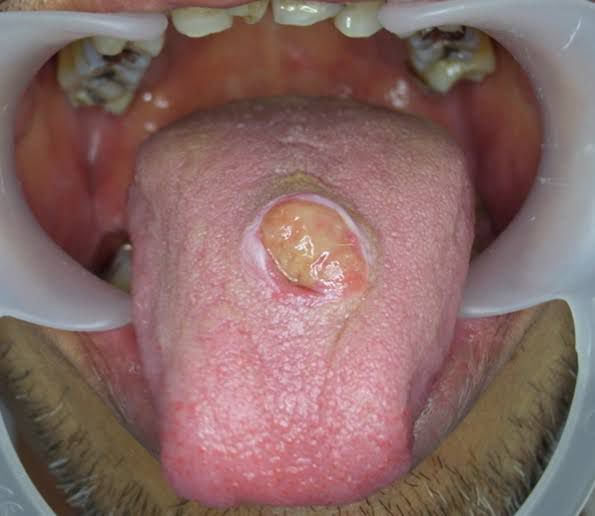

Adenosquamous carcinoma (ASC) is a rare malignant tumor of the oral and maxillofacial region characterized by mixed squamous and glandular differentiation and aggressive clinical behavior, such as extensive local invasion, recurrence, and rare metastasis By: .https://images.app.goo.gl/RYWX3d31ginCwyMa8